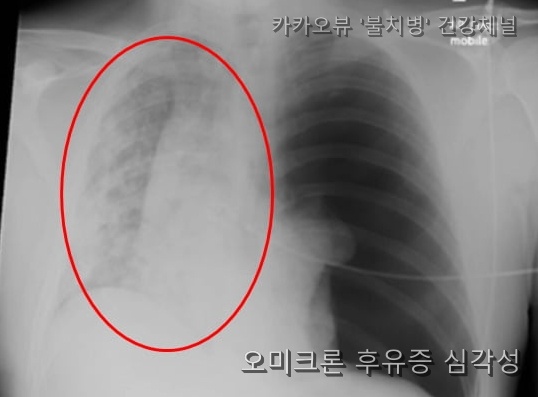

오미크론은 위증증이 아니라, 경증 이후 후유증의 심각함이다.

경증을 겪은 환우 분들의 패를 한번 보았는가?

경증을 겪고도 정상으로 신체가 돌아왔다고 자신하는 기사는 왜 없을까? 기준이 모두 잘못되었다. 다시금 더 심각한 기준을 두고, 방역에 노력해야 할 시기다.